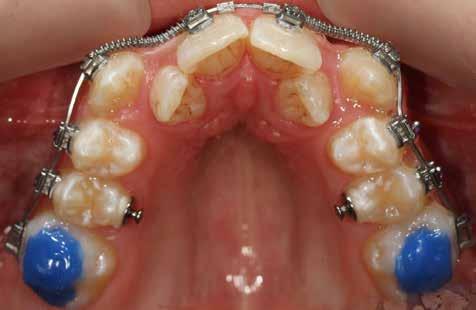

A Pitts21-es fix készülékes kezelés során a harapásemelőket a felső nagyőrlő fogakra ragasztottuk, hogy a felső molárisok intrúziójával segítsék a harapás zárását (8. kép) Ún. keresztharapásos, majd később normál class 2-es gumihúzással (9–10. képek), továbbá az elülső fogakon alkalmazott ún. Rainbow harapás-záró gumihúzással (11. kép) korrigáltuk a jobb oldali teljes premolárisnyi distal-harapást, valamint az elülső nyitott harapást.